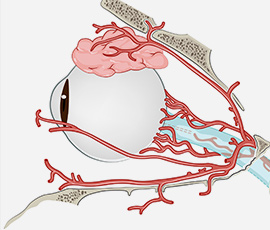

从眼内结膜

进行微小切口,

外部无疤痕可见 -